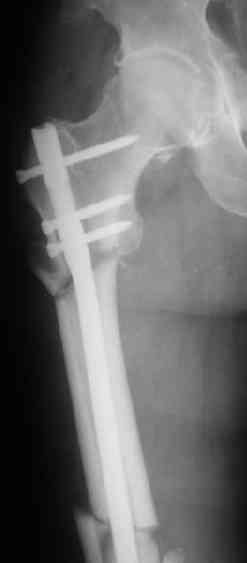

> денамизация - февраль 2006. ( 3 и 4 снимки) на сегодняшний день (снимок 5) беспокоит боли в тбс...

Однозначно: удалить, рассверлить, перештифтовать более толстым гвоздем. ЭТОТ 9 мм будет? Возьмите 12-14.

Дистально обязательно два винта! Проксимально можно один динамический. Больной будет счастлив на следующий же день!

Учитывая точку введения - верхушка б\вертела - что бы исправить варус взял бы соответствующий гвоздь: длинную Гамму или PFN или Recon

Судя по уровню перелома, винты в шейку избыточны, подойдет и диафизарный гвоздь. Все, что нужно, это тиски и труба. Загнуть сразу ниже отверстий градусов на 8-10, и вся недолга. Последние годы у нас это рутинная практика. Предызогнутые еще с завода гвозди неудобны тем, что они уже правый-левый.

Согласен, что 3,5 см укорочение этим снимкам не соответствует, за счет перелома и деформации - 1,5 см от силы. То есть либо ошибка измерения, либо приводящая контрактура, либо укорочение за счет другого отдела.

Согласен, что закрытый реостеосинтез с рассверливанием и коррекцией оси - это то, что надо. Мы бы ввели в центральный отломок статических 2-3 винта, и один динамический винт в дистальном отломке.

Если имеете доступ к trochanteric медуллярным штифтам TAN Smith Nephew или DePuy, где имеется offset на 8 градусов для удобства черезвертельного введения и профилактики нарушения кровеснабжения

головки (см. снимок) можно было применить штифт, в котором опороспособность достигается за счет блокирующих шурупов сверху и снизу.

Учитывая, что ложный сустав с укорочением, для восстановления необходимо применение дистракции (на кольцах или femoral distractor) или другой методикой, например после определения длины, штифт вводят в канал, не снимая Insertion tool, блокируется дистально шурупами и дальше штифт доводится до желаемого положения, затем через jig

производят блокировку проксимально